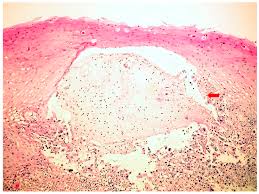

Hsv Esophagitis Pathology / Pathology Of The Esophagus - Peptic strictures cause a gradually progressive dysphagia for solid foods.. Common forms of esophagitis include reflux esophagitis, infectious esophagitis, pill esophagitis candida esophagitis (see the image below) is the most common type of infectious esophagitis. Cytomegalovirus esophagitis is a form of esophagitis associated with cytomegalovirus. The latter can occur frequently during anesthesia or deep sedation. Herpes esophagitis is a viral infection of the esophagus caused by herpes simplex virus (hsv). The esophagus is a tube composed of a mucosal lining, and longitudinal and circular smooth muscle fibers.

Pathology Of Herpes Simplex Virus Infection Dr Sampurna Roy Md from www.histopathology-india.net This condition occurs in the setting of patients with a weakened immune system who are susceptible. Esophagitis can occur from irritation from toxic or abrasive materials ingested or from gastric reflux. Infective esophagitis is a rare disease, affecting mostly immunocompromised patients. Very few cases of a multiple viral infection have been reported. Cobblestone esophagitis (эзофагит со слизистой булыжной мостовой). The latter can occur frequently during anesthesia or deep sedation. Healing and relapse of severe peptic esophagitis after treatment with omeprazole. Causes of esophagitis include stomach acids backing up into the esophagus, infection, oral medications and allergies.

Cytomegalovirus esophagitis is a form of esophagitis associated with cytomegalovirus. Herpes esophagitis is a viral infection of the esophagus caused by herpes simplex virus (hsv). Herpes esophagitis is a viral infection of the esophagus caused by herpes simplex virus (hsv). Symptoms include dysphagia, upper abdominal pain, diarrhea, nausea, vomiting, and sometimes hematemesis. Very few cases of a multiple viral infection have been reported. Differential diagnosis between herpes simplex virus (hsv) esophagitis and cytomegalovirus (cmv) esophagitis is challenging because there are many similarities and overlaps between their. Common forms of esophagitis include reflux esophagitis, infectious esophagitis, pill esophagitis candida esophagitis (see the image below) is the most common type of infectious esophagitis. Swallowed food and liquids normally pass through it. Eosinophilic esophagitis attributed to gastroesophageal re. Infective esophagitis is a rare disease, affecting mostly immunocompromised patients. Healing and relapse of severe peptic esophagitis after treatment with omeprazole. Esophagitis can occur from irritation from toxic or abrasive materials ingested or from gastric reflux. The esophagus is a tube composed of a mucosal lining, and longitudinal and circular smooth muscle fibers.

Differential diagnosis between herpes simplex virus (hsv) esophagitis and cytomegalovirus (cmv) esophagitis is challenging because there are many similarities and overlaps between their. Esophagitis can cause painful, difficult swallowing and chest pain. Healing and relapse of severe peptic esophagitis after treatment with omeprazole. Esophagitis can occur from irritation from toxic or abrasive materials ingested or from gastric reflux. Causes of esophagitis include stomach acids backing up into the esophagus, infection, oral medications and allergies. The latter can occur frequently during anesthesia or deep sedation. Very few cases of a multiple viral infection have been reported. Herpes esophagitis is a viral infection of the esophagus caused by herpes simplex virus (hsv). Esophagitis may cause odynophagia and even esophageal hemorrhage, which is usually occult but can be massive. We present a case of combined cytomegalovirus. Eosinophilic esophagitis attributed to gastroesophageal re. Swallowed food and liquids normally pass through it. Esophagitis, also spelled oesophagitis, is a disease characterized by inflammation of the esophagus.